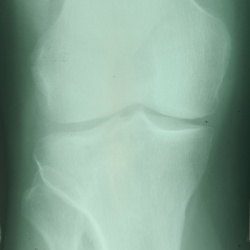

Ребенок 16 лет, девочка. Боли в коленных суставах. Коллеги как можно дифференцировать данный  дефект костной ткани ?